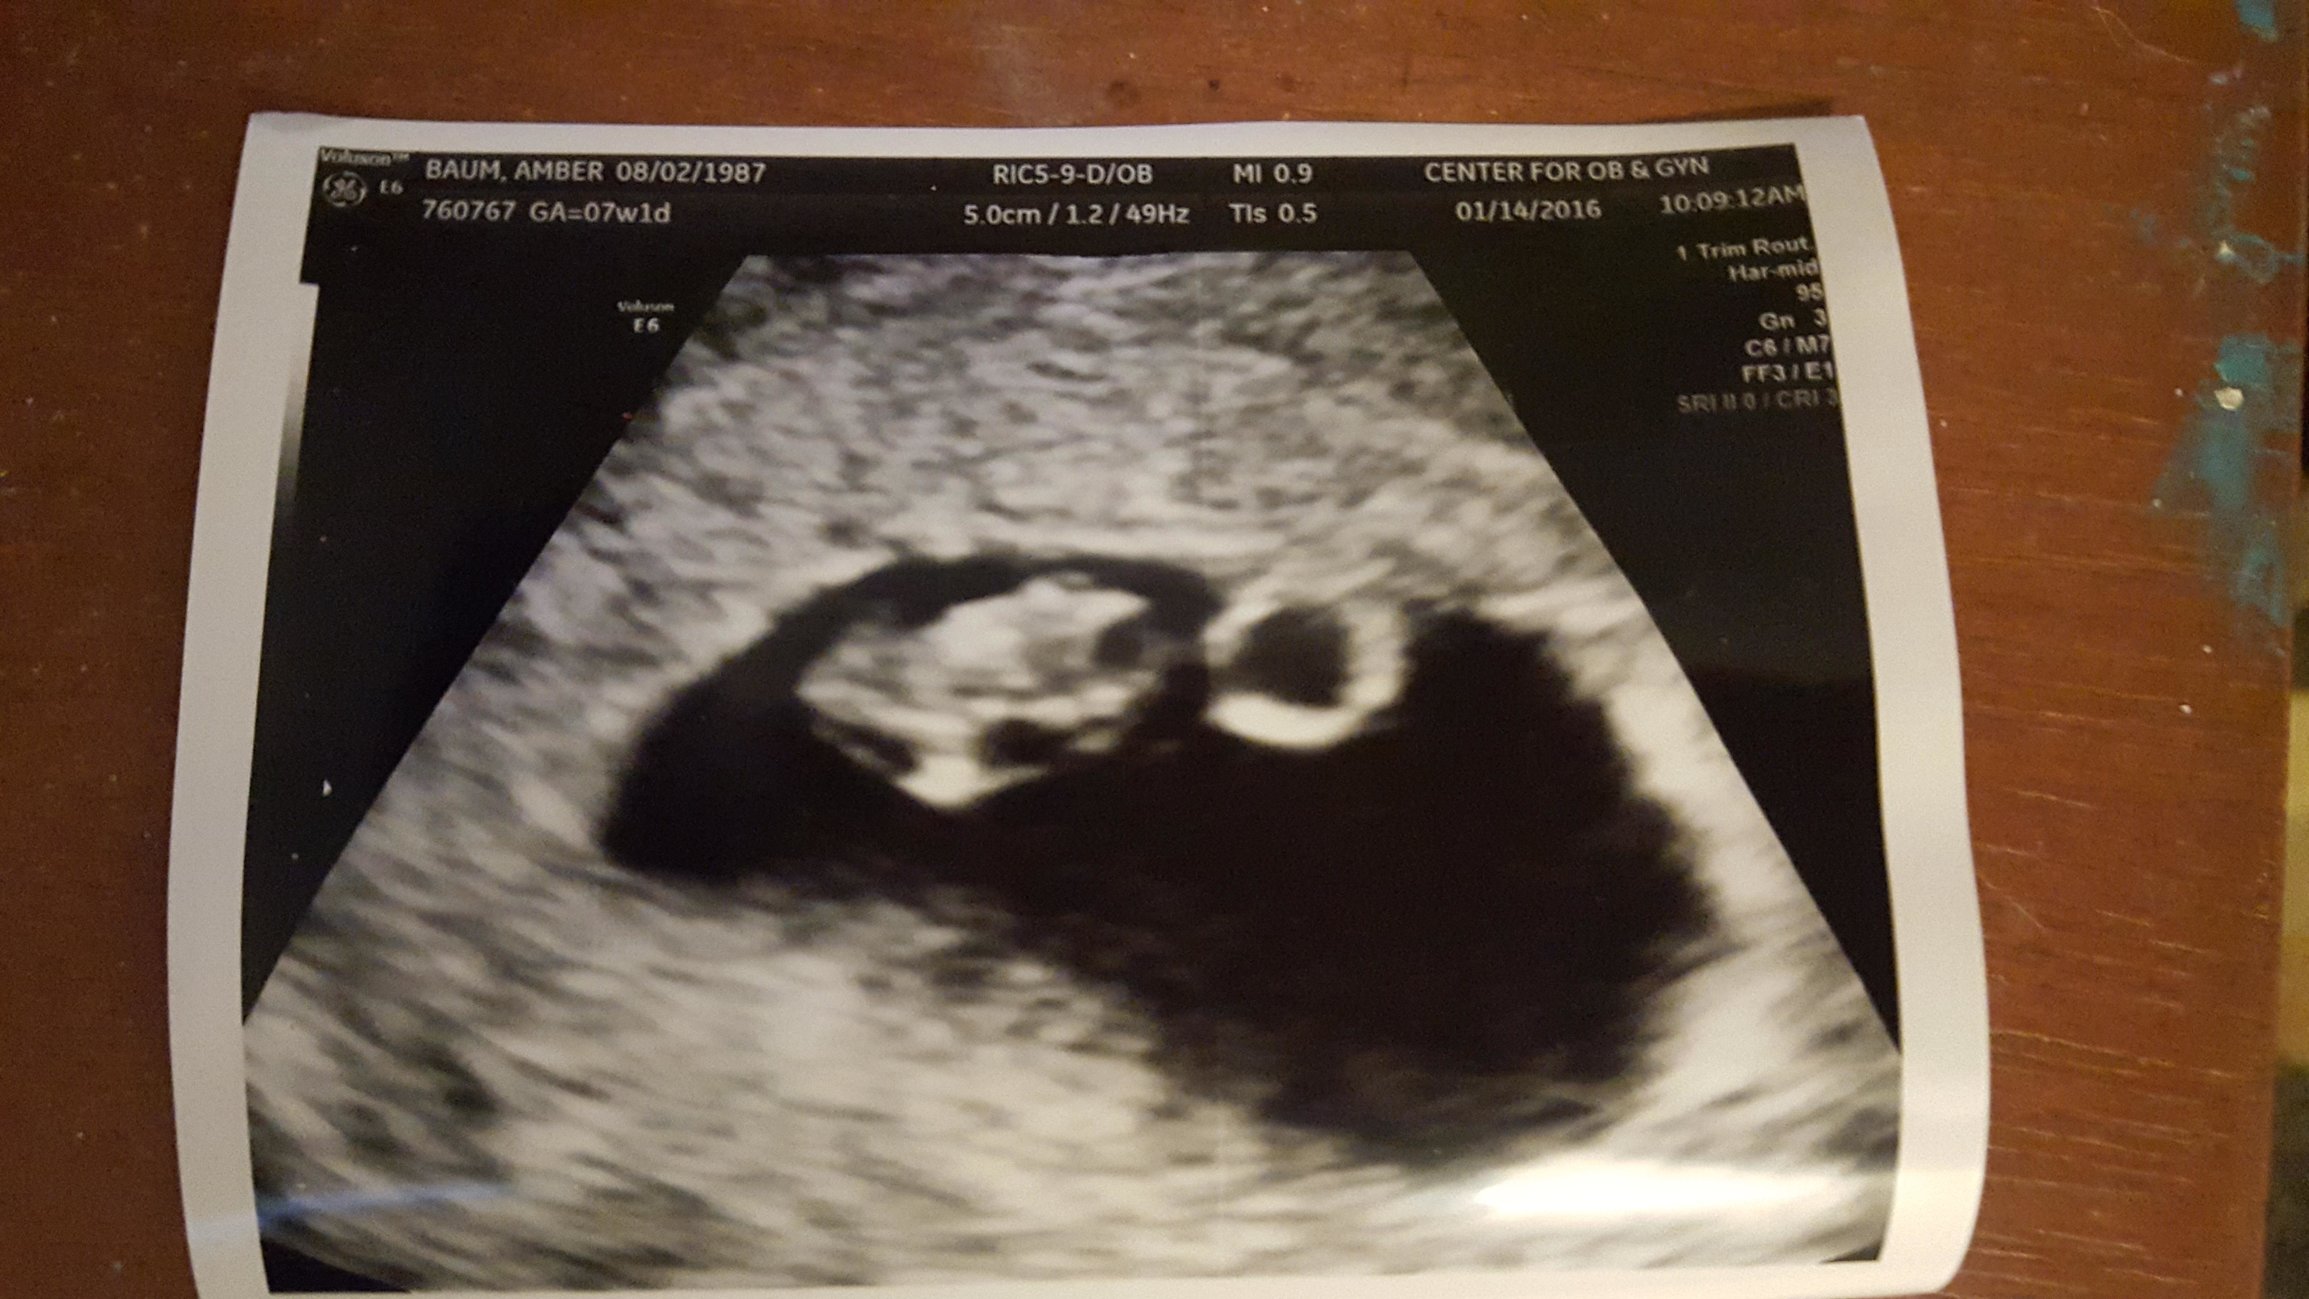

First ultrasound at 7 weeks and I've tried to read up on the RAMZI method but am so confused can someone help read this it was a vaginal ultrasound

• From what I remember of the journal article, the ultrasound was at 6 weeks for the researchers to analyze. But it doesn't look anything like my US at 7 weeks for the first pregnancy so I'd guess girl just based on it being opposite.

• I thought it was related to where you were implanted. So in order to get information you would need to have asked the sonogram tech where baby implanted in your uterus.  It was true for me for my last 2 babies, didn't ask about my first.  We'll see about this one!